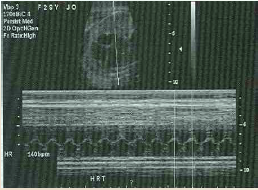

Purpose of it is to : Documents fetal, Viability, Heart Rate, Varies throughout pregnancy - Normal Range (110 to 180 bpm (JDMS May/) or 120-160 HA)

M-Mode

motion mode

What steps do you need to take to perform M-Mode? (8)

Where does the cursor need to be placed for m-mode?

Place cursor through the atrial and ventricular wall to allow simultaneous display of cardiac wall motion